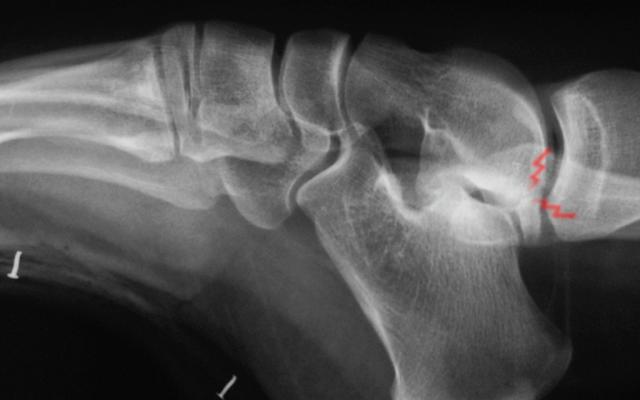

Osteochondral fracture?

45 year old male. ankle inversion injury 3 days ago